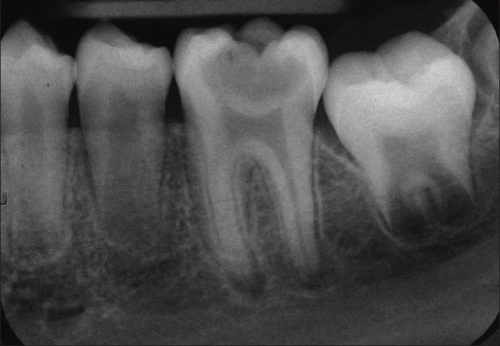

Phim Xquang quanh chóp cho thấy sâu răng đến tuỷ

Khi bị sâu răng chạm đến tủy, bạn có thể phải điều trị tủy răng